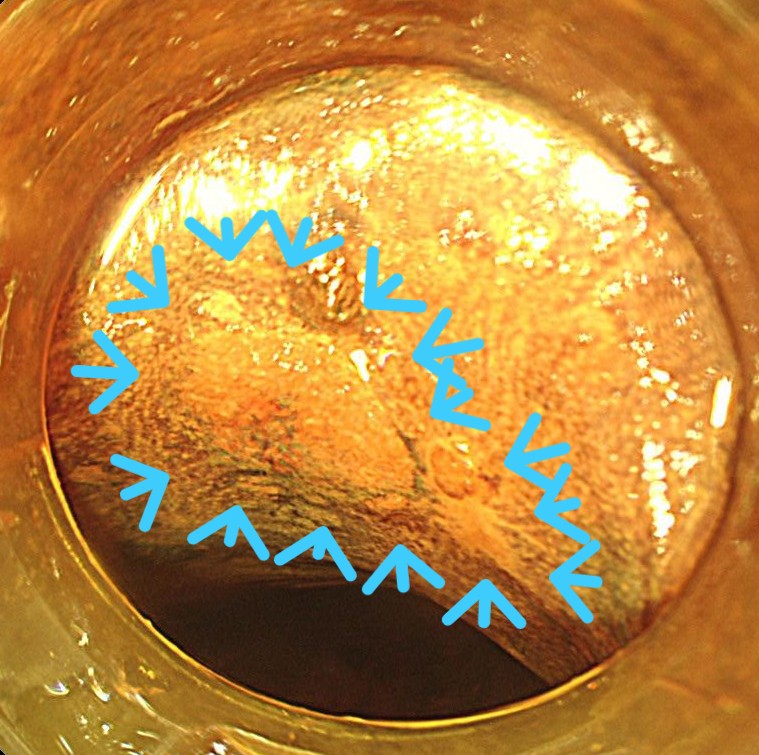

同部位はルゴール染色しますと不染域であり、コントラストがはっきりします。

腫瘍周囲のマーキングを開始します。バイオ300のフォーストコアグ10で全周にマーキングをします。デュアルナイフを用いています。